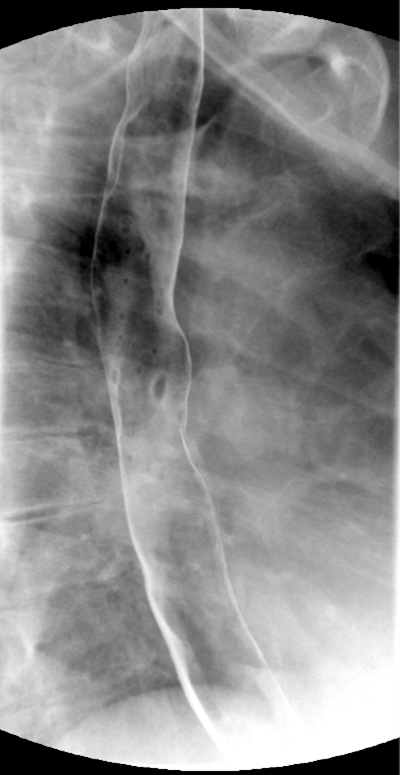

- After the patient has begun drinking, take images of the upper and lower esophagus distended and coated with barium

(key image 5)

(key image 6)

(key image 7).

- Thoracic images are obtained in the upright RPO and LPO projections after the adminstration of bubbly barium (EZ Gas followed by thick barium).

- The goal of these images is to see the thoracic esophagus distended and coated with barium. This may not be possible with one image and make take several to accomplish.